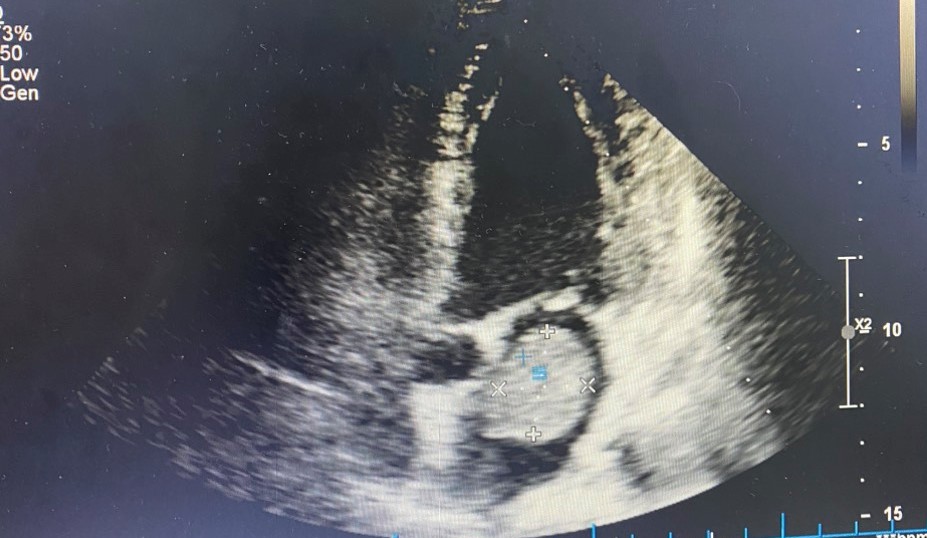

Bệnh nhân nữ 55 tuổi ở Đại Thắng, Tiên Lãng, Hải Phòng có tiền sử tăng huyết áp. Cách đây 2 tháng, người bệnh xuất hiện đau vùng lưng, đau tăng dần kèm tê bì vùng đùi phải. Ngày 16/5, người bệnh đến khám và được chẩn đoán thoát vị đĩa đệm L4,5, thoái hóa cột sống thắt lưng, có chỉ định phẫu thuật. Trước phẫu thuật, người bệnh được khám, đánh giá chuyên khoa tim mạch. Bất ngờ, hình ảnh siêu âm tim phát hiện bệnh nhân có khối u nhầy nhĩ trái kích thước lớn 3,8 x 2,7 cm dính vào vách liên nhĩ, di động làm hẹp một phần van hai lá trong thì tâm trương, nguy cơ ảnh hưởng đến huyết động cao.

- Hình ảnh u nhầy nhĩ trái qua siêu âm